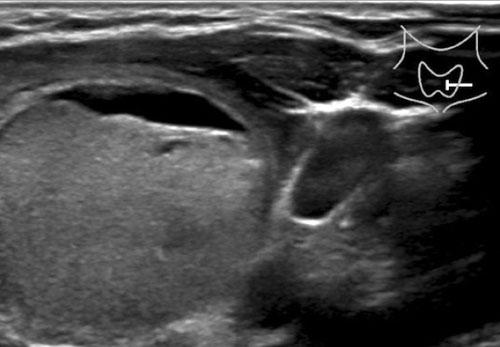

Trường hợp 2

Quan sát hình ảnh và xác định điểm TI-RADS.

Cuộn hình ảnh để xem điểm TI-RADS.